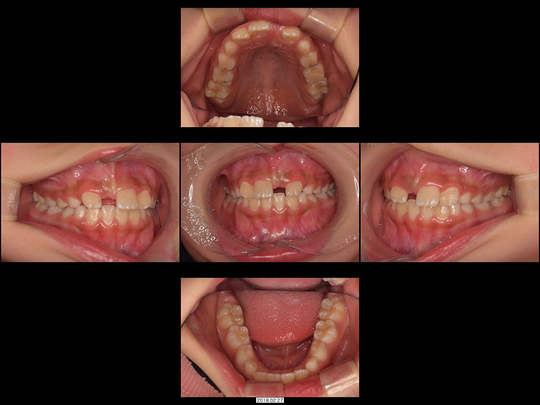

Sさん 初診時9歳 女性

矯正前

治療の説明

上の前歯2本が生えてこないのを心配しておられたのに、「様子見しましょう」とずっと言われ続けてお困りでした。中には「大学病院でしか対応できません」と言われたこともあったようです。

CT検査の結果、歯が歯ぐきの中に埋まった埋伏(まいふく)といわれる状態でした。歯ぐきだけでなくあごの骨まで歯に被さっていたため、埋伏している前歯の表面を傷つけずにあごの骨まで削り、引っ張り出すための外科処置(外科的開窓牽引による矯正)を行いました。奥歯の乳歯から永久歯への生え変わりのスペースもないので、あわせてあごの骨も拡大しています。

40か月、40回

541,000円

リスクや副作用:出血を伴う可能性があります。治療後に、痛みや腫れ、出血を引き起こす可能性があります。

装置に慣れるまでに1週間ほどかかる可能性があります。歯列を広げる過程で少し痛みを感じる可能性があります。装着時に多少しゃべりづらくなる可能性があります(2~3週間ほどで慣れます)。